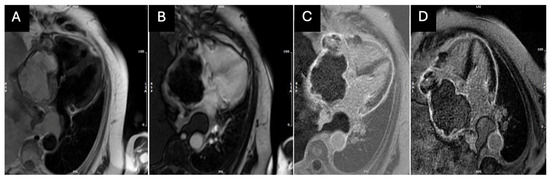

2. Case Presentation